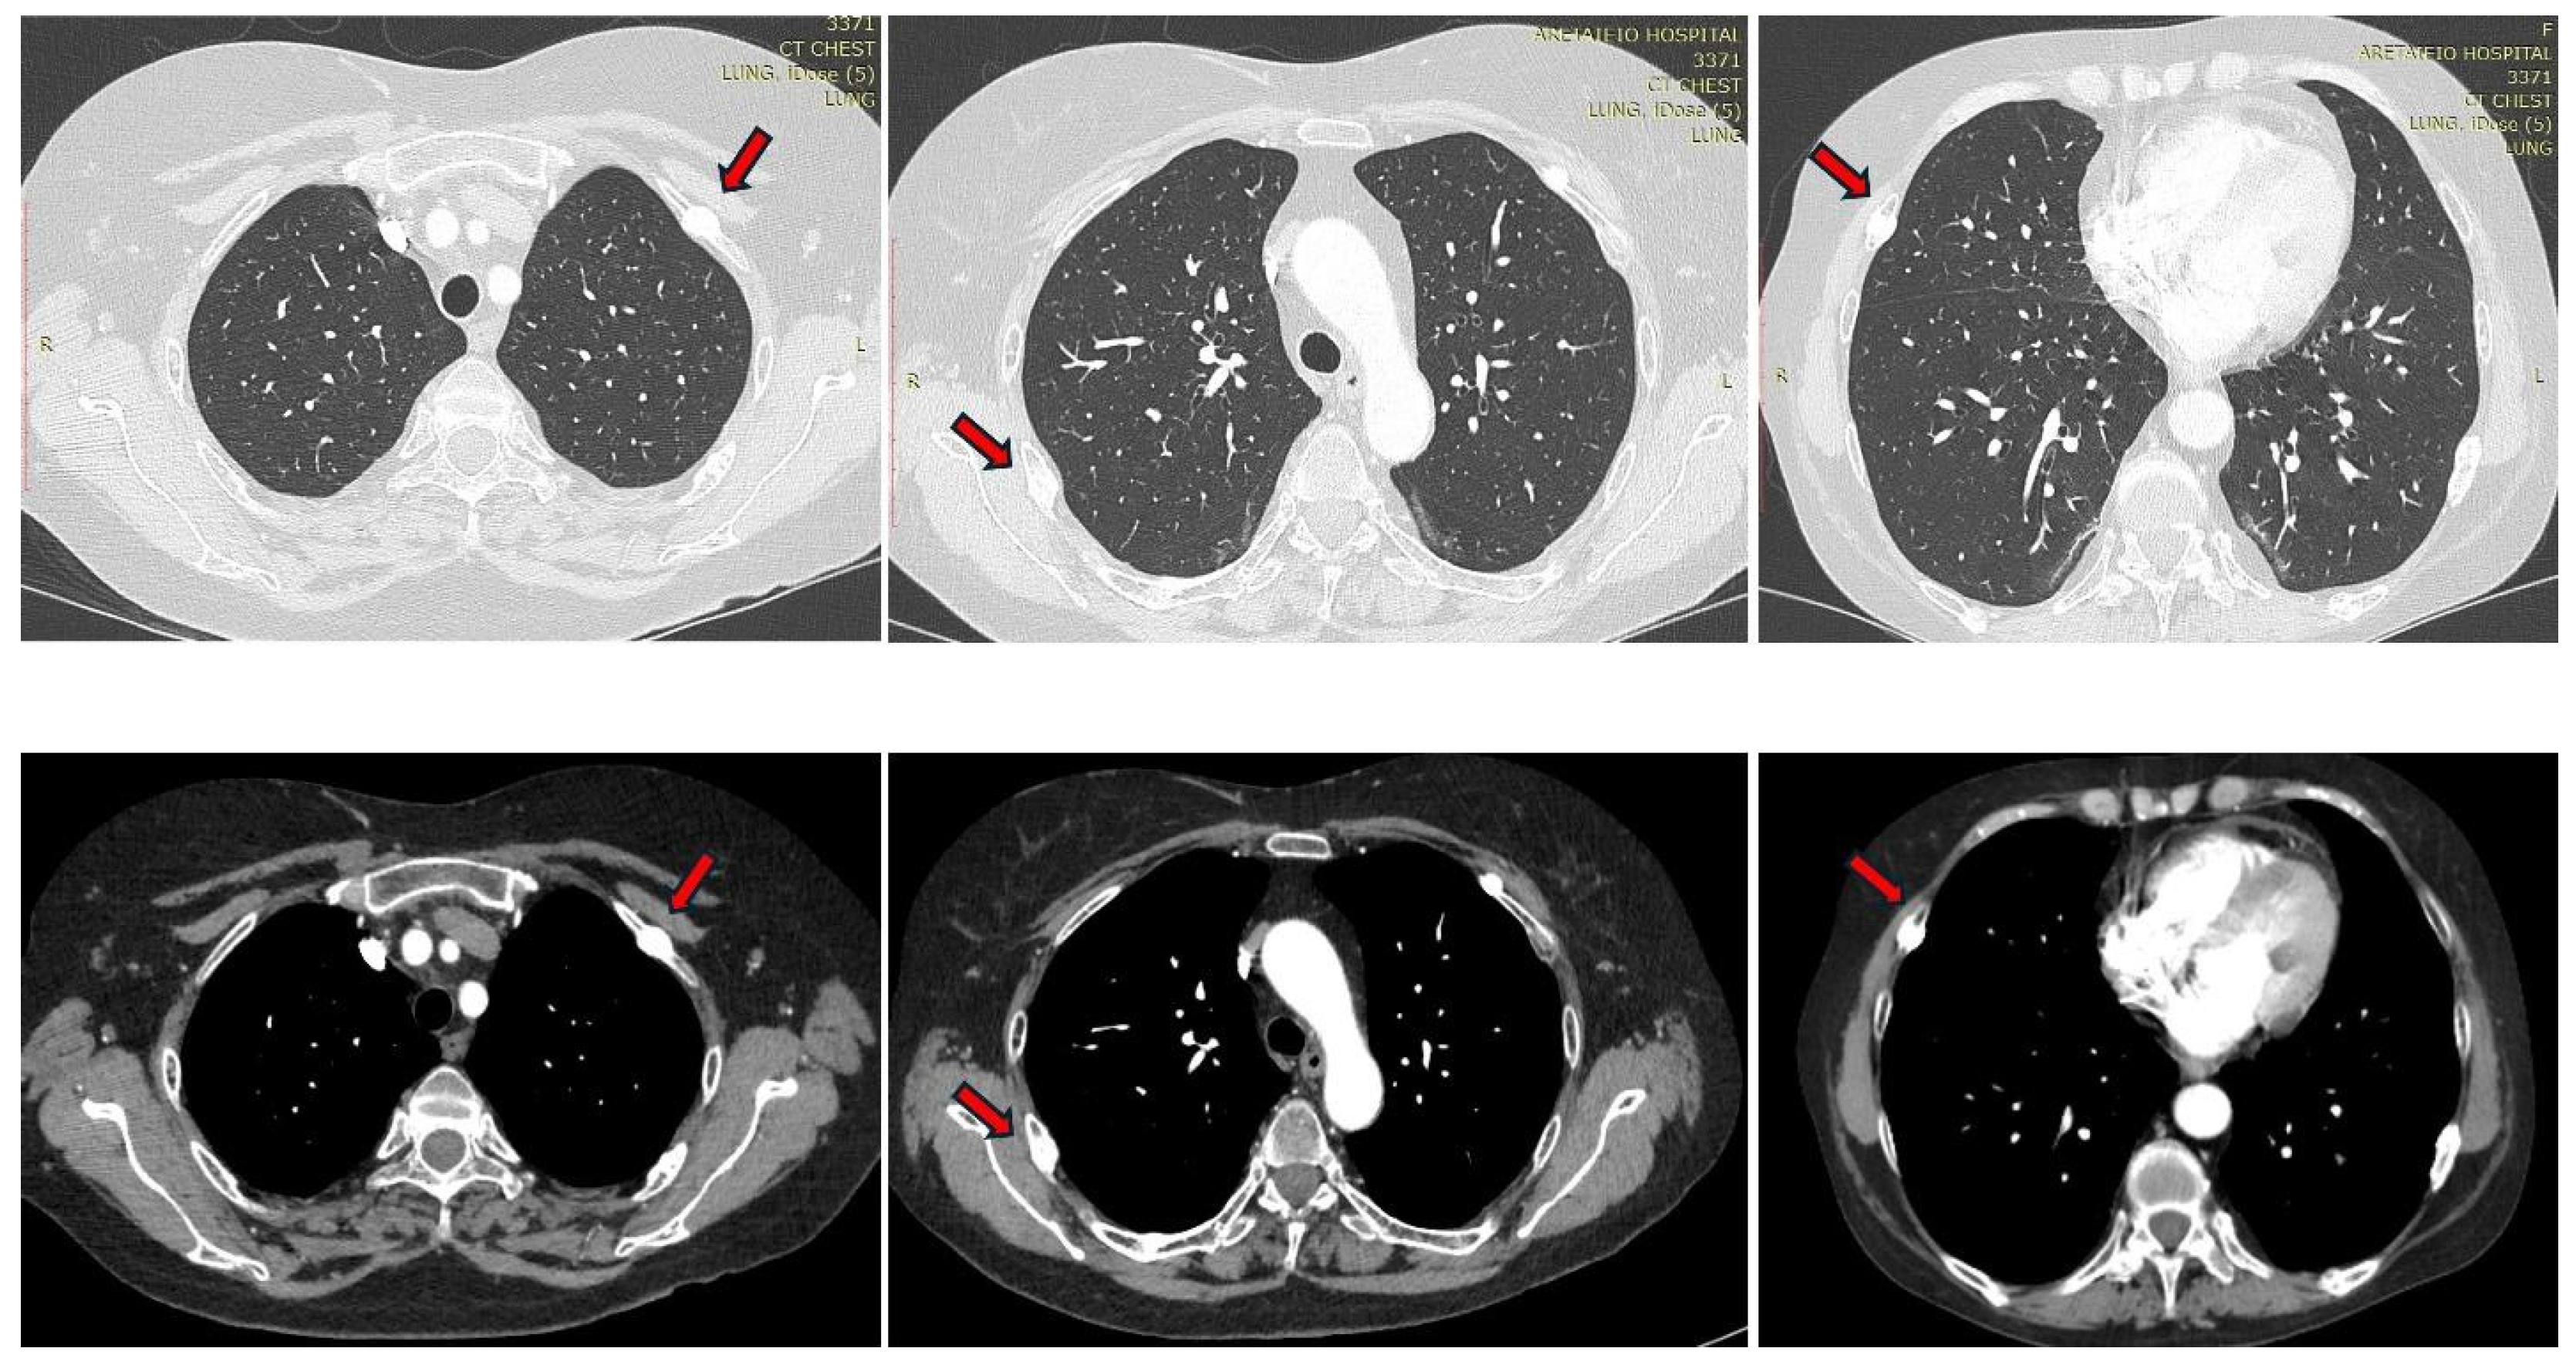

| Present case | Adrenal adenoma | 46 | F | sternum, middle phalanges of both indicators, rib, vertebral fractures T11, L1, sacrum | T-score lumbar −3.8 | Arterial Hypertension, Dyslipidemia, Diabetes | 395 μg/24 h | <2.4 pg/mL | 16.7 μg/dL (<1.8 μg/dL) |